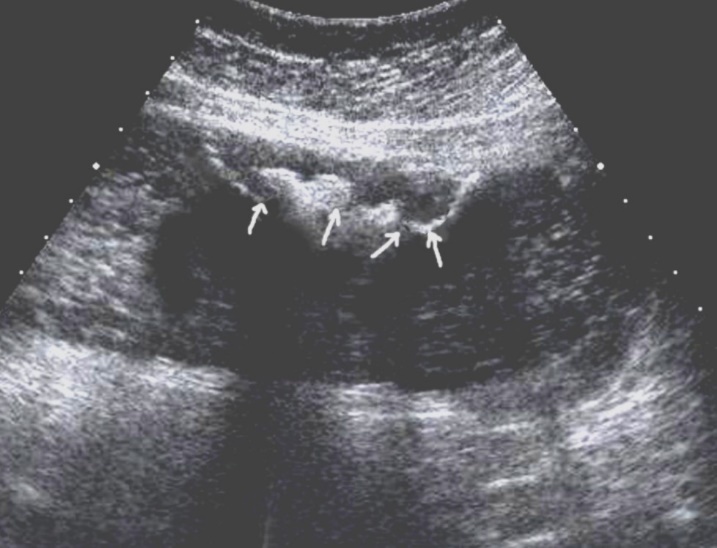

T3 stage of polypoid form was recorded in one case, ulcerative form – in 11 cases, infiltrative ulcerative forms – in 21 cases and diffused infiltrative forms – in 8 cases. The Sonographic features of infiltrative ulcerative form of gastric carcinoma was shown as local uneven thickening of the stomach wall with a length of up to several centimeters with intermittent images and ulceration of the mucosa (Figure 11). The Ulcerative form of gastric carcinoma was shown as a raised margins surrounded by a thickened gastric wall with irregular margins (Figure 12). Gastric carcinomas of diffuse infiltrative form is illustrated as a diffuse thickening of the muscle layer, a smooth contour, discontinuous mucosal image without ulceration and involvement of the serous membrane in the process (Figure 13).

Figure 13.Gastric carcinomas of diffuse infiltrative form in the posterior wall of the stomach body of stage T3. The tumor is manifested by diffuse thickening of the muscle layer, a smooth contour, discontinuous mucosal image without ulceration and involvement of the serous membrane in the process. An enlarged, altered lymph node of low echogenicity, round shape, without differentiation of the peripheral and central part, is visualized behind the stomach.